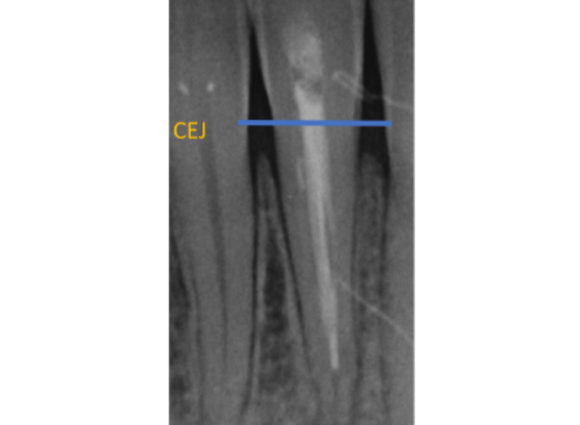

Figure 1: Pulp canal obliteration (PCO). The patient had trauma to UL1 15 years ago and developed a yellow discolouration over time. She was keen to improve the appearance of the tooth. The UL1 was asymptomatic and did not respond to sensibility testing.

Radiographically, UL1 had a normal PDL width and an intact lamina dura could be seen around the tooth. A diagnosis of pulp canal obliteration was reached for UL1. There was no endodontic infection and the patient was advised to have external tooth whitening; this will take longer and a veneer might be necessary if a satisfactory result can’t be achieved with external whitening alone. Figure 1a: Preoperative photograph. Figure 1b: Preoperative radiograph.